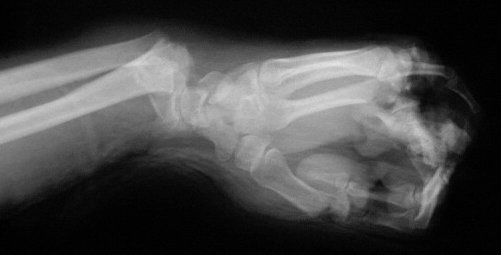

The thumb was lengthened over a period of six weeks with an external fixator.

Xrays at the beginning and end of the distraction process.